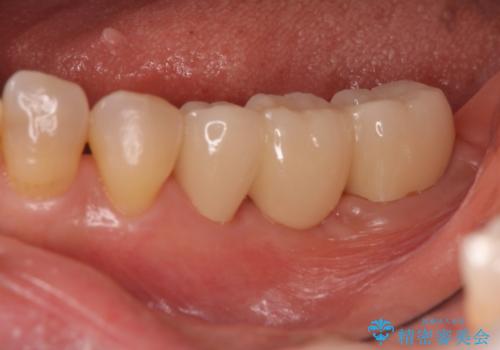

- 63.8万円 左下部分矯正27.5万円 奥歯ブリッジ36.3万円(仮歯1.1万円×3本 ジルコニアクラウン11万円x3本)費用は治療当時の料金となります

奥歯の部分矯正を行うことで、歯の傾きが良くなり、結果神経を取らずにブリッジを入れていくことができました。

通常矯正治療後は歯並びが戻らないように保定が必要ですが、ブリッジを入れているので歯並びは戻らないため保定が不要です。

部分矯正と補綴の相性は良いといえます。